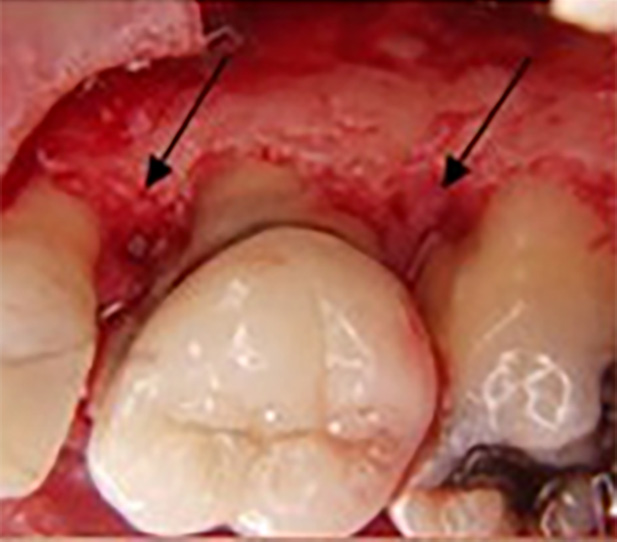

The gum is pulled up during this treatment, and the plaque is removed. In some cases, the irregular surfaces of the damaged bone are smoothed.

This limits the areas where pathogenic bacteria can hide. Then, the gums are placed so the gum tissue is wholly connected to the tooth. Removing the space between the gums and teeth also reduces the growth areas of harmful bacteria. The likelihood of severe health problems leading to periodontal disease is reduced.